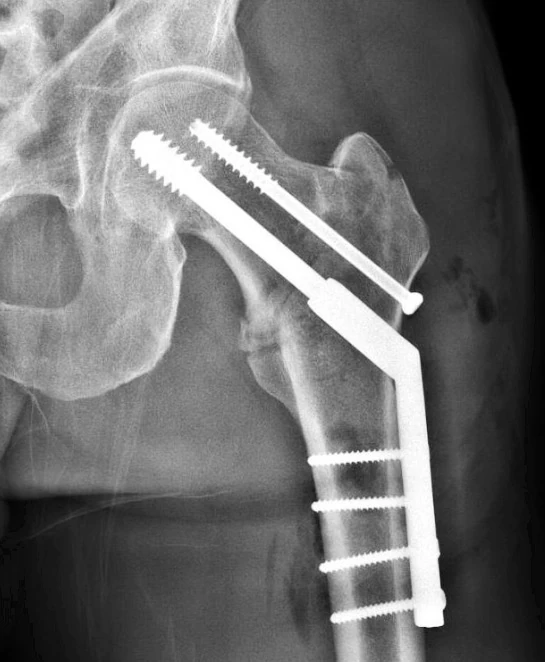

The title of this post isn’t quite accurate. It should have been, released from the hospital. I didn’t have to sneak out or anything. My guy, Doctor Karam came by yesterday morning and we had a good talk. He told me that the surgery went as perfect as it can go. He said that he was confident that if I had the ability to stand on my leg that it would be strong enough to hold my weight and that he doesn’t foresee any issues. Man, this guy is one of the chosen few. I was very fortunate to get excellent counseling from my friend Stacie, which connected me to Dr. Karam. He is so good that I’m going to use him for my follow-up appointments, even though it is a 6 hour drive.

Great to see you do so well. I do feel you are cutting a lot of surgeons short for calling your surgeon “one of the chosen few” for a repair that seems the standard of practice for a fracture like that. Looks nice on the film for sure.

MV-No insult intended at all to other ortho surgeons. But, just like all occupations, there are okay surgeons to great ones. Dr. Karam is on staff, at one of the best teaching hospitals in the country. Plus, it is a level one trauma center, so they see many more surgical cases from accidents, like mine. It is very hard to get a residency at this hospital in surgery. It is nearly a given he is the best of the best in his field.